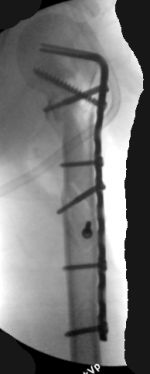

Re: Многооскольчатый перелом плеча

Although we can not see exactly the head piece, and assuming that there are not signs of infection, my suggestion would be to do some type of "bridging" procedure : implant fixation in head piece and distal main fragment, and the rest to be left on its soft tissue attachments (living bone graft).

I just did this attached case, using 90 degrees angled blade plate, and this would be my preference in all similar cases.

Two days ago, I had to plate TWO humeral NONUNIONS after intramedullary nailing. Just to remove them from proximal end, significant damage had to be done to the rotator cuff. My belief is (and supported by the most of recent literature) is that the plating is a better option for humeral fractures.